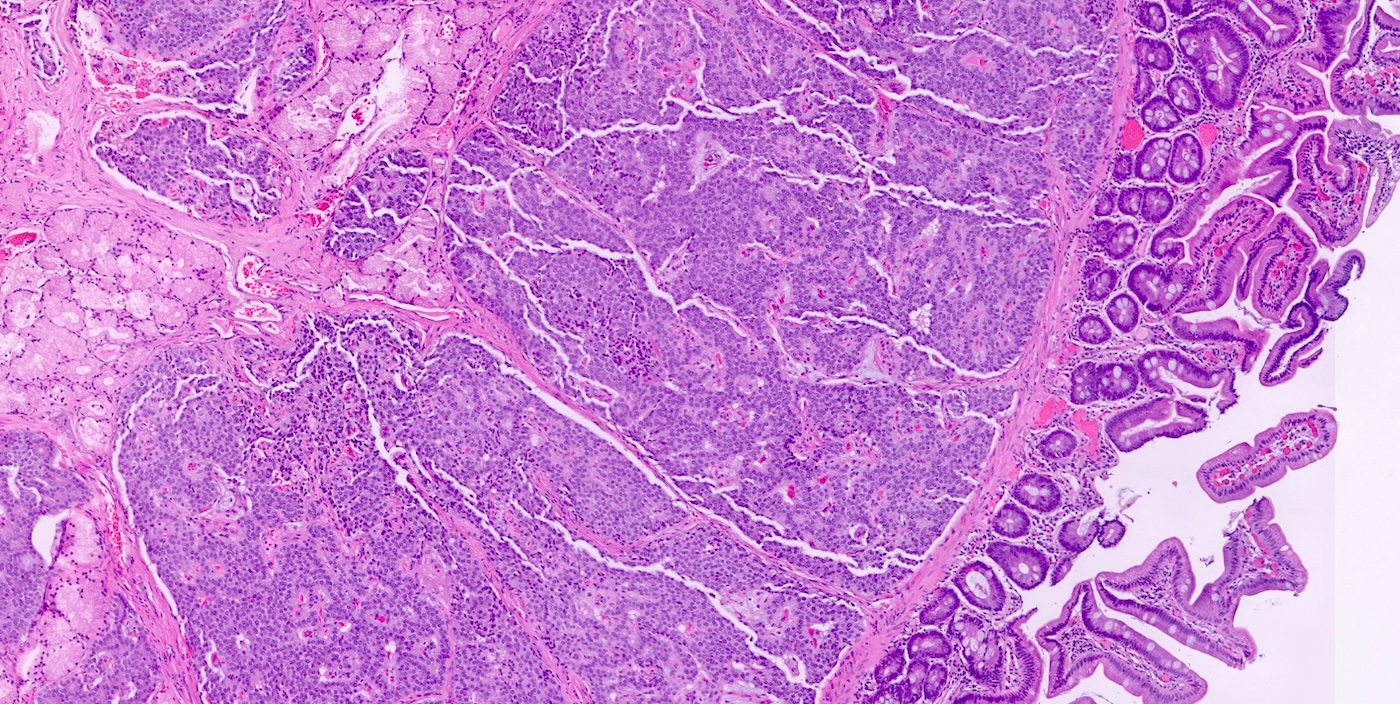

- Pancreatic neuroendocrine tumors

- Well differentiated NETs composed of uniform polygonal cells with eosinophilic or clear cytoplasm, salt and pepper chromatin (finely granular nuclear chromatin) (Arch Pathol Lab Med 2025 Mar 4 [Epub ahead of print])

- Immunohistochemical staining positive for chromogranin A, synaptophysin and neuroendocrine markers (Arch Pathol Lab Med 2025 Mar 4 [Epub ahead of print])

- Some tumors may show vascular invasion or mitotic activity, indicating more aggressive potential

- Diffuse islet cell hyperplasia occurs frequently (World J Gastroenterol 2011;17:137)

- Multiple pancreatic microadenomas or microtumors are a common feature of MEN1 associated PanNETs and serve as a useful clue to the diagnosis of MEN1